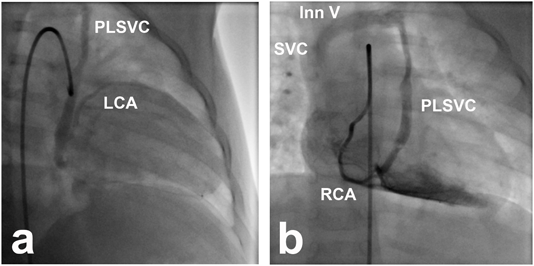

A one-year-old girl is followed in our outpatient clinic for aortic valve stenosis without coronary arteries nor coronary sinus abnormalities assessed by X-ray, ECG and echocardiogram examinations. To further characterize her disease, cardiac catheterization was performed. Abnormal venous return of coronary blood flow was detected on ascending aortography. Angiogram of the left coronary artery (LCA) revealed drainage to right atrium (RA) via the vertical vein, known as a persistent left superior vena cava (PLSVC), innominate vein (Inn V) and superior vena cava (SVC) (Fig. 1a). Right coronary artery (RCA) blood flow also returned to the RA via the same circulation (Fig. 1b) and to a lesser degree, via the normal coronary sinus. When a Swan-Ganz balloon catheter was placed in the PLSVC for the vessel occlusion, dynamic T-wave changes were noted in leads III and aVf on the electrocardiogram (ECG), suggestive of transient myocardial ischemia with PLSVC balloon catheter occlusion (Fig. 2). The T-wave changes were actually smaller than we expected. The reasons of this are possibly incomplete vessel occlusion and persistent normal anatomical circulation from coronary sinus to RA.

Fig. 1 Coronary venous return from LCA and RCA

Venous return from a) LCA and b) RCA drained to RA via PLSVC, Inn V and SVC.